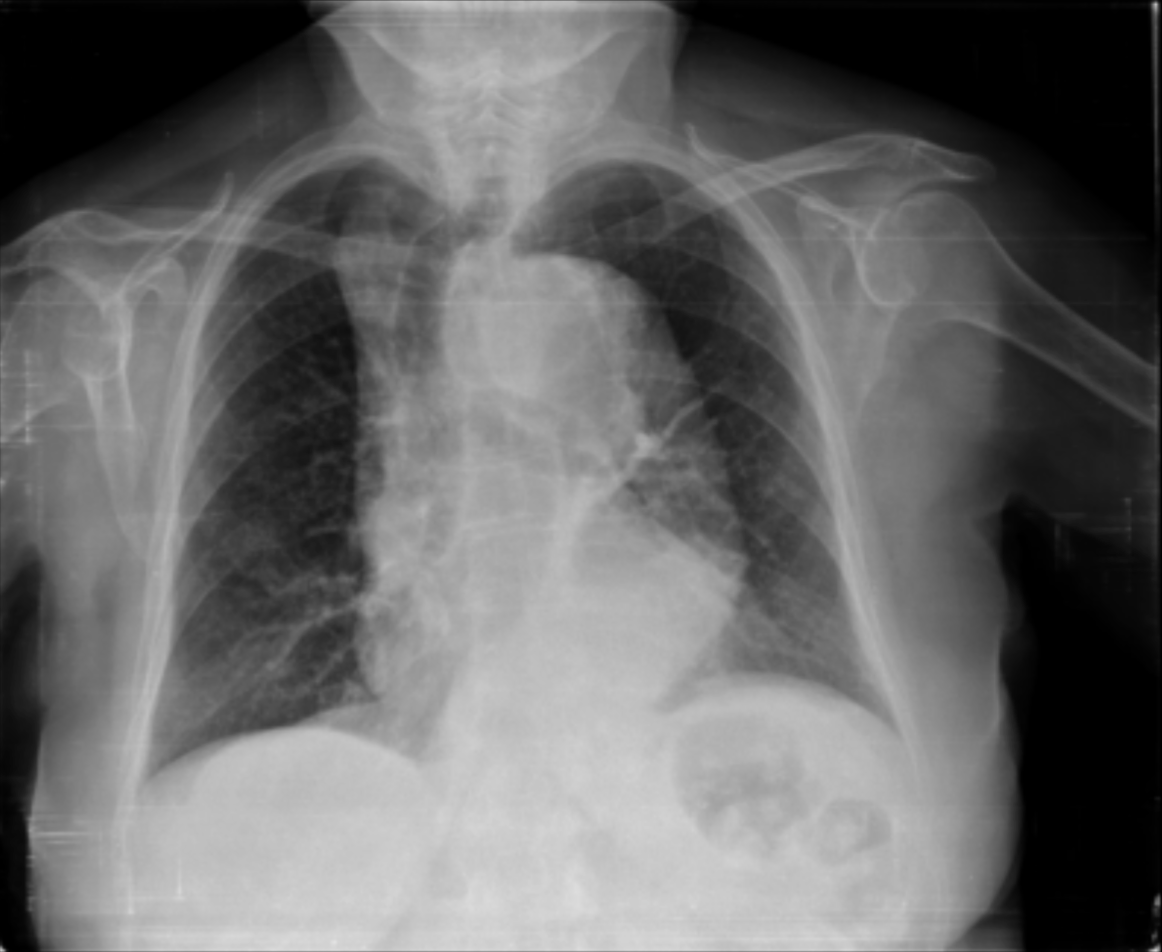

4.3.3 Visual grounding

In this section, we evaluate RadVLM’s visual grounding capabilities, which could help clinicians localize specific regions or pathologies on a CXR. This is particularly useful once a pathology has already been identified – either by a radiologist’s input or through our previously described AI tasks – since it allows one to pinpoint exactly where the abnormality appears on the image.

We report performance metrics for the three main grounding tasks RadVLM was trained on: anatomical grounding using the Chest Imagenome test set, abnormality grounding using the VinDr-CXR test set, and phrase grounding using the MS-CXR test set (Table 1). For each task, we use mean Average Precision (mAP) as our primary evaluation metric.

As mentioned in Table 2, some of the CXR-specific VLMs already have grounding capabilities. CheXagent was trained to handle both abnormality and phrase grounding tasks, while MAIRA-2 – originally trained to produce radiology reports with grounded observations – is also capable of predicting bounding box coordinates when provided with input text. After retrieving each model’s instruction template for generating bounding box coordinates (Appendix 1-Table 2), we evaluated both CheXagent and MAIRA-2 on all three grounding tasks performed by RadVLM.

Our results show that RadVLM performs well at localizing anatomical regions (e.g., “right lung”, “aortic arch”, illustrated in Figure 5a), achieving a mAP of 85.8 %, by far surpassing the other CXR grounding models (Table 4). This advantage is partly explained by including the Chest Imagenome dataset (and thus the anatomical grounding task) in the training set, which CheXagent and MAIRA-2 did not leverage. However, it remains a key feature for any grounding model to possess a fine-grained understanding of CXR anatomy.

For the abnormality grounding task, RadVLM is less consistent (Figure 5b), likely due to higher sparsity of abnormality locations and labels, yet it still achieves best performance (Table 4). For the phrase grounding task, while MAIRA-2 and CheXagent demonstrate great performance, RadVLM surpasses them with a mAP of 81.8% (Table 4), presumably benefiting from the newly released PadChest-GR dataset (Castro et al.,, 2024) used for training.

Overall, these results show that our instruction tuning strategy for visual grounding (covering three essential tasks), combined to a modern VLM backbone, offers a promising avenue to help clinicians localize anatomical and pathological features during a CXR exam. Furthermore, providing fine-grained details within an LLM-generated output may also enhance the ability to answer grounded questions in a multi-turn setting, as we explore next.

b. Abnormality grounding

thickening

fibrosis

enlargement

lung disease